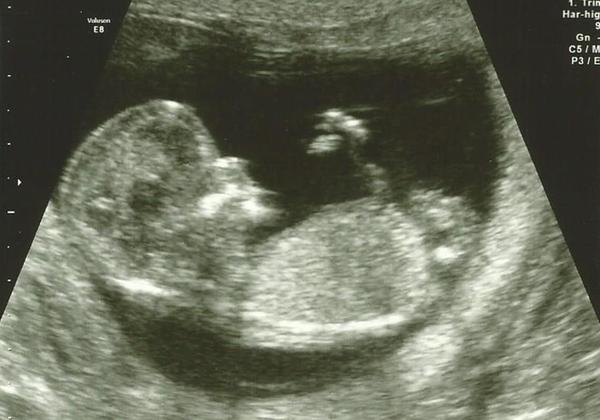

Ahoj holky, hlasím se po screeningu. Miminko je zdravé, máme 58mm a odpovídáme 12+4tt, takže TP 25.4. UTZ byl super a doktor nám toho spoustu ukázal. Nosní kůstka je přítomna a dostatečně velká, fronto-maxilární úhel v normě, šíjové projasnění 0,9mm, falx cerebri se zobrazuje (to je něco v hlavě nebo mozku), páteř i horní čelist v pořádku bez rozštěpů, srdce pracuje dobře, obě komory s normální kontraktilitou, aorta i plicnice se zobrazují, srdeční frekvence pravidelná 140-160 tepů/min., žaludek v dutině břišní, močový měchýř plodu naplněn, končetiny plodu přítomny, normální pohybová aktivita plodu. V kombinaci s krví vyšlo riziko vývojových vad 1:50 000 🙂 A řekl nám i pohlaví a to se podržte - vypadá to na kluka. Moje analytické odhady selhaly. Manžel tomu zatím ani nevěří, ale já jsem tam hodně dobře viděla pinďoura i s kulkama. Manžel se zeptal, jestli to nemůže být pupečník a doktor se jen smál, že určitě ne.